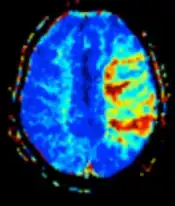

Diffusion weighted (DWI) Conventional DWI Measure of Brownian motion of water molecules.[66] High signal within minutes of cerebral infarction (pictured).[67]

Apparent diffusion coefficient ADC Reduced T2 weighting by taking multiple conventional DWI images with different DWI weighting, and the change corresponds to diffusion.[68] Low signal minutes after cerebral infarction (pictured).[69]

Perfusion weighted (PWI) Dynamic susceptibility contrast DSC Measures changes over time in susceptibility-induced signal loss due to gadolinium contrast injection.[72]

• Provides measurements of blood flow

• In cerebral infarction, the infarcted core and the penumbra have decreased perfusion and delayed contrast arrival (pictured).[73]